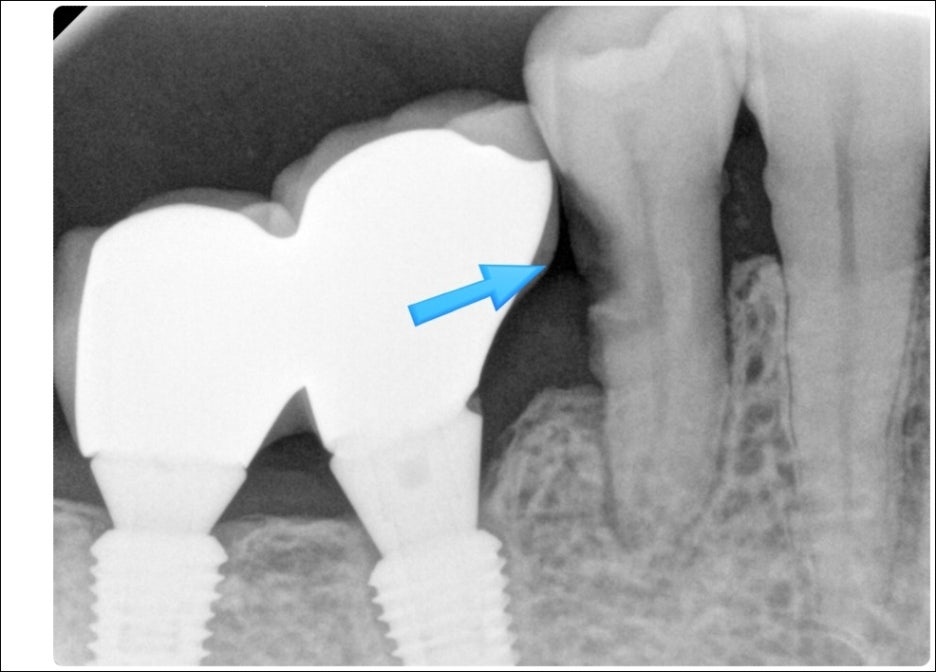

한 환자분의 경우, 임플란트 주변 앞니 뿌리 쪽에 충치가 발생한 상태로 내원하셨습니다.

방사선 사진에서도 확인되었듯이 치아 뿌리 부위는 구조적으로 얇고 신경과 가까워

충치가 빠르게 진행될 수 있는 위치입니다.

하지만 당시에는 통증이 없다는 이유로 치료를 미루시고 경과를 지켜보시겠다고 하셨습니다.

약 1년 뒤, 통증이 심해진 상태로 다시 내원하셨습니다.

재촬영한 영상에서는 이전보다 충치 범위가 훨씬 넓어져 있었고,

실제 치료 과정에서 확인된 상태는 엑스레이보다 더 깊고 광범위하게 진행되어 있었습니다.

특히 치아와 잇몸이 만나는 부위까지 충치가 퍼지면서 치아 구조 자체가 매우 약해진 상태였습니다.